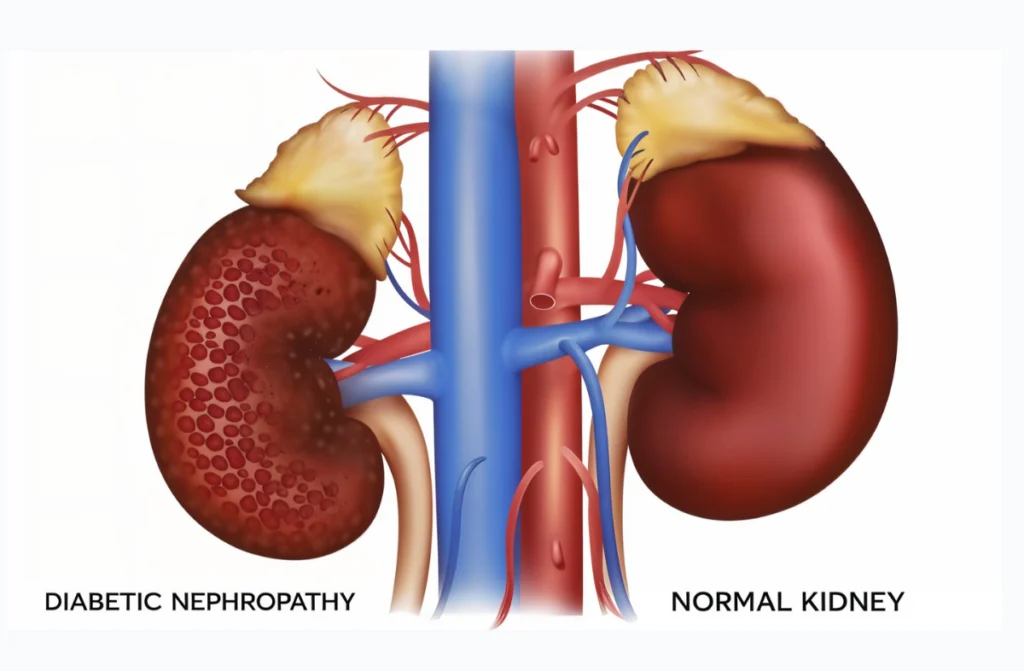

Diabetic kidney disease (also known as diabetic nephropathy) is a complication of diabetes that affects the kidneys’ ability to filter waste from the blood. High blood sugar levels over time can damage the tiny blood vessels in your kidneys, making them leaky and less efficient. This condition often develops slowly and may not show symptoms until the kidney function is significantly impaired. It’s one of the most common causes of chronic kidney disease and kidney failure, but early detection can slow or even stop its progress.

Diabetic kidney disease develops gradually over several stages. Understanding where you stand helps in taking timely action. Each stage tells us how well your kidneys are working and how far the damage has progressed.